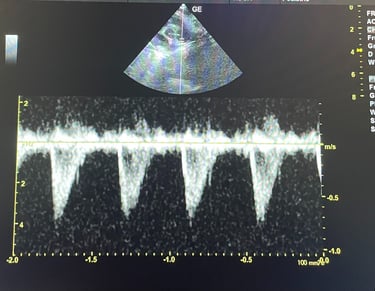

BADANIE ECHOKARDIOGRAFICZNE: badanie serca przy użyciu wysokiej klasy sprzętu ultrasonograficznego, który umożliwia wykrycie wad wrodzonych, chorób zwyrodnieniowych zastawek, powiększenia serca.